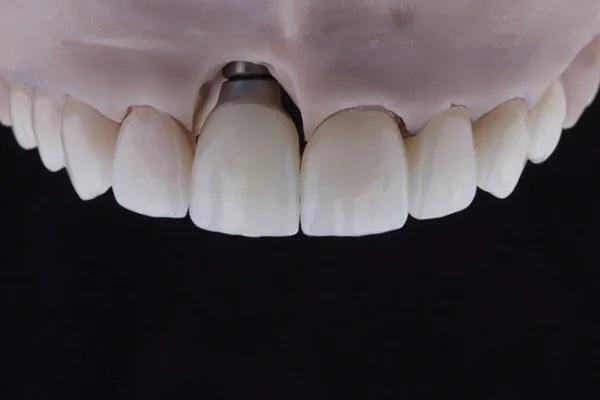

С помощью библиотеки цифровых имплантатов был разработан индивидуальный гибридный абатмент. Все коронки были спроектированы на основе конструкции абатмента и отфрезерованы. После фрезерования изготовленного на заказ гибридного абатмента из диоксида циркония (Ceramill Zolid HT+, Amann Girrbach) желаемого оттенка, который был похож на соседние подготовленные зубы, его спекали в течение ночи. Коронки были обработаны прессуемым воском для изготовления реставраций на основе дисиликата лития (GC Initial LiSi Press, GC America).

Циркониевый абатмент был отрегулирован, а выступающий профиль коронки, контактирующий с мягкими тканями был отполирован, чтобы обеспечить идеальную интеграцию тканей. Затем абатмент был прикреплен к аутентичному титановому основанию с помощью связующего материала двойного отверждения (G-CEM LinkForce, GC America) в соответствии с инструкциями производителя.

Коронки были установлены на штампы для 3D-печати моделей и абатмент. Цифровой аналог был вставлен в 3D-модель. Следует отметить, что цифровые аналоги должны быть практически согласованы с цифровой библиотекой в программном обеспечении CAD/CAM. Цифровые аналоги должны быть той же марки, что представлены в библиотеке цифровых имплантатов, поскольку колпачки для интраорального сканирования всегда виртуально связаны с библиотекой цифровых имплантатов. Переход на другую марку потребует перехода в другую библиотеку.

Фото 12. Примерка окончательных реставраций на модели.

Фото 13. Окончательная реставрация после полировки и глазирования.